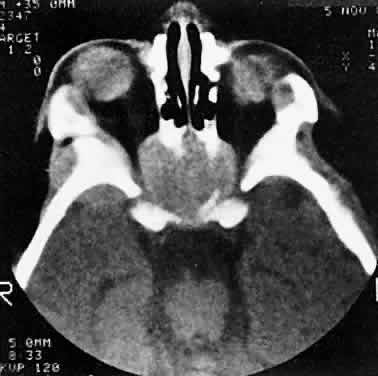

Orbital myositis may represent a greater proportion of cases of IIPT in childhood than in adulthood, and involvement of multiple extraocular muscles may occur more frequently in children than inadults. In orbital myositis, early diplopia and increased discomfort with attempted eye movement are typical symptoms. CT may show enlargement of one or more extraocular muscles in one or both orbits (Figs. 21 and 22). When a single muscle is involved, the specter of a primary or metastatic neoplasm within the muscle may be raised. However, external inflammatory signs, considerable pain and limited motility, and an explosive onset of symptoms within 24 hours all suggest orbital myositis. The uniform enlargement of the muscle, including its tendinous insertion (see Fig. 22), also helps distinguish the process from a neoplasm, which might be expected to produce a more focal, globular expansion. Echography may support the diagnosis of inflammation by showing edema in the episcleral space as a relative sonolucency between the scleral and orbital fat echoes (Fig. 23). Its CT counterpart is an increase in the radiodensity and thickness of the ocular tunica.

Fig. 21. A. This 16-year-old boy had acute onset of bilateral proptosis, pain, diplopia, chemosis, and conjunctival injection. B. Bilateral enlargement of the superior and medial rectus and inferior oblique muscles. Other sections showed similar involvement of other extraocular muscles.